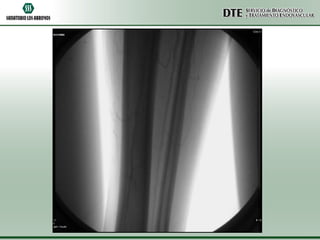

ATPP

•Utilizando una guía hidrofílica de 0.035” se atravesó la obstrucción total crónica y

sobre la misma guía se avanzó un catéter cobra 5F el cuál fue posicionado a nivel del

tronco peroneo.

•Se realizó un test angiográfico a dicho nivel, no comprobándose permeabilidad. No

se visualizaron el llenado de las arterias tibial anterior, tibial posterior ni peronea.

•Se intercambió la guía hidrofílica por una guía de 0.014” y utilizando un catéter de

trombo aspiración Export 6F, se realizó trombo aspiración mecánica a nivel del

segmento ocluido.

•Se logró aspirar gran cantidad de material trombótico fresco, a pesar de lo cuál no

pudo recanalizarse exitosamente la obstrucción total.

•Debido al riesgo de comprometer con microembolias la circulación colateral, se

decidió dar por terminado el procedimiento.

•El control angiográfico final demostró una sensible mejoría a nivel de la circulación

colateral con un llenado más rápido de la arteria pedia y el arco plantar.

ATPP •Utilizando una guíahidrofílica de 0.035” se atravesó la obstrucción total crónica y sobre la misma guía se avanzó un catéter cobra 5F el cuál fue posicionado a nivel del tronco peroneo. •Se realizó un test angiográfico a dicho nivel, no comprobándose permeabilidad. No se visualizaron el llenado de las arterias tibial anterior, tibial posterior ni peronea. •Se intercambió la guía hidrofílica por una guía de 0.014” y utilizando un catéter de trombo aspiración Export 6F, se realizó trombo aspiración mecánica a nivel del segmento ocluido. •Se logró aspirar gran cantidad de material trombótico fresco, a pesar de lo cuál no pudo recanalizarse exitosamente la obstrucción total. •Debido al riesgo de comprometer con microembolias la circulación colateral, se decidió dar por terminado el procedimiento. •El control angiográfico final demostró una sensible mejoría a nivel de la circulación colateral con un llenado más rápido de la arteria pedia y el arco plantar.